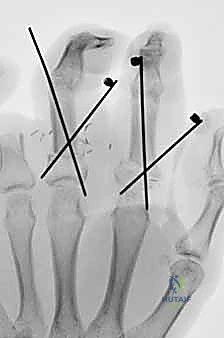

2. بتر أصابع متعددة: لإنقاذ ما يمكن إنقاذه للحفاظ على قدرة اليد على الإمساك والقبض.

الأساس المتين هو أول خطوة في البناء. يقوم الدكتور هطيف بتقصير العظام قليلاً (Bone Shortening) لتخفيف الشد على الأوعية الدموية والأعصاب عند توصيلها. يتم تثبيت العظام باستخدام أسلاك كيرشنر المعدنية (K-wires)، أو مسامير دقيقة، أو صفائح معدنية صغيرة. التثبيت يجب أن يكون قوياً ليسمح ببدء العلاج الطبيعي المبكر.